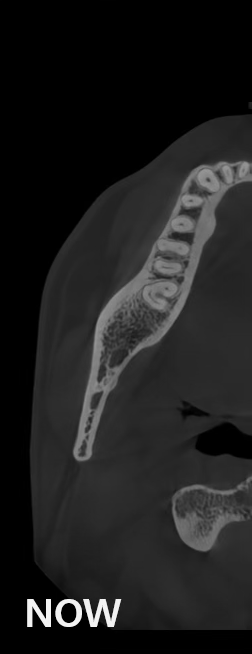

Công nghệ video của HDXWILL liên tục được cập nhật thông qua quá trình nghiên cứu không ngừng.

Một thuật toán toán học phản ánh các đặc điểm vật lý của Chụp cắt lớp vi tính chùm tia X (CBCT) và một công cụ AI tiên tiến học từ nhiều dữ liệu khác nhau sẽ phối hợp với nhau để giảm nhiễu và thể hiện cấu trúc răng rõ ràng hơn.

Các hiện vật kim loại được xóa bằng công nghệ AI và cấu trúc răng, mão kim loại và cấy ghép được phục hồi chính xác dựa trên các nguyên tắc toán học.